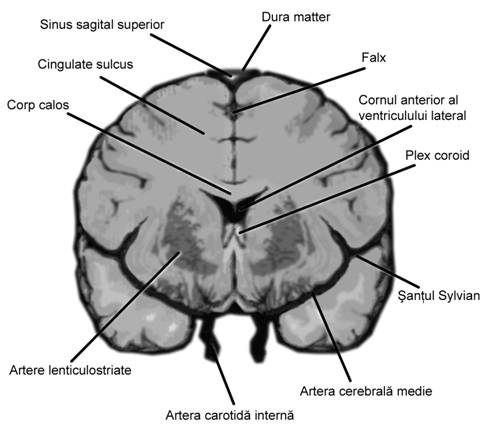

Fig. nr.163. Schita anatomica a creierului in sectiune coronala (frontala ). (adaptat dupa Pooh in [7])